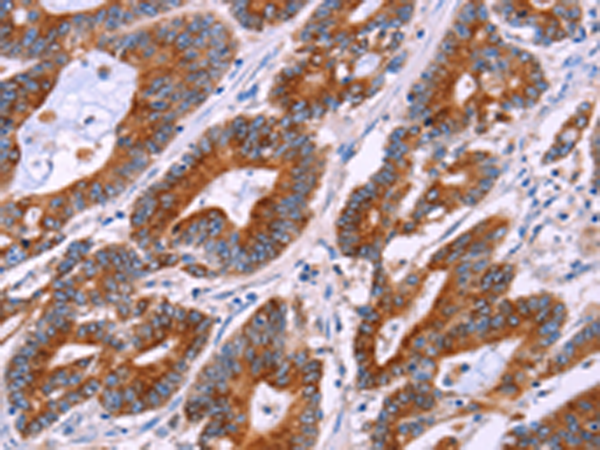

分类: 科研抗体货号: P11265别名: MUC-6应用: IHC反应种属: Human